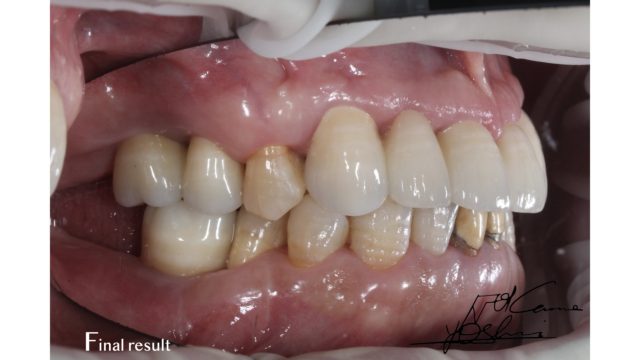

お口の左側、BEFORE写真です。

お口の左側、AFTER写真です。